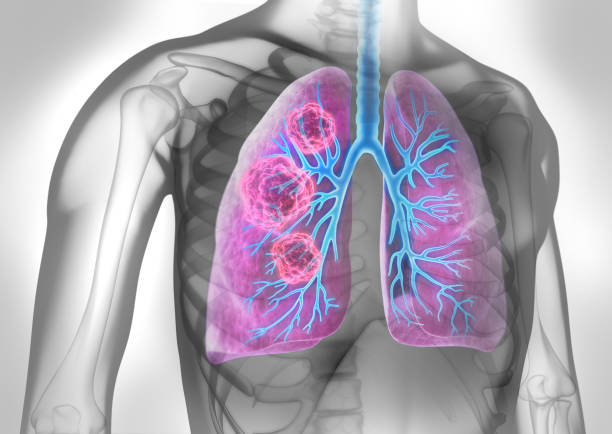

폐암은 초기에는 증상이 미미하거나 없을 수 있습니다. 그러나 조기에 발견하고 진단받으면 치료의 성공률이 훨씬 높아집니다. 초기에 폐암을 발견하면 조기 치료를 시작하여 종양의 성장과 전이를 제한할 수 있습니다. 뿐만 아니라, 치료에 있어 다양한 치료 방법을 활용할 수 있어 폐암 초기 증상을 잘 알고 있는 것이 중요합니다.

흉통 또는 가슴 불편감은 폐암 초기증상 중 하나입니다. 이 증상은 폐암이 주변 조직이나 신경에 압력을 가하거나 신경근을 침범할 때 발생할 수 있습니다. 흉통은 가슴의 어디에서든 발생할 수 있으며, 무증상에서 심한 통증까지 다양한 정도가 있을 수 있습니다. 때로는 흉통이 호흡과 관련되어 심해지거나 호흡 곤란과 동반될 수도 있습니다.